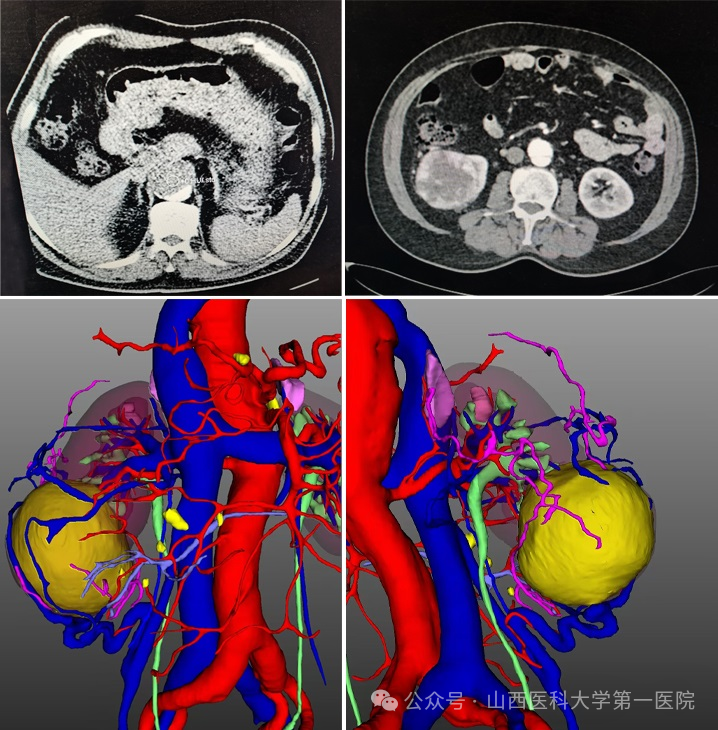

术前血管造影

65岁男性患者因右肾肿瘤合并主动脉夹层、主动脉弓支架植入术后入院。完善相关检查后发现,患者瘤体位于右肾下极,大小约7cm,虽然1月前曾于外院行主动脉弓支架置入术,但检查显示目前存在支架内漏和支架内血栓,且主动脉弓降主动脉移行处至双侧髂总动脉分叉处动脉夹层,主动脉弓、胸、腹主动脉及分支弥漫粥样硬化性病变。同时患者既往合并有高血压、脑梗等基础疾病,病情复杂、凶险、棘手。

术前影像及三维模型